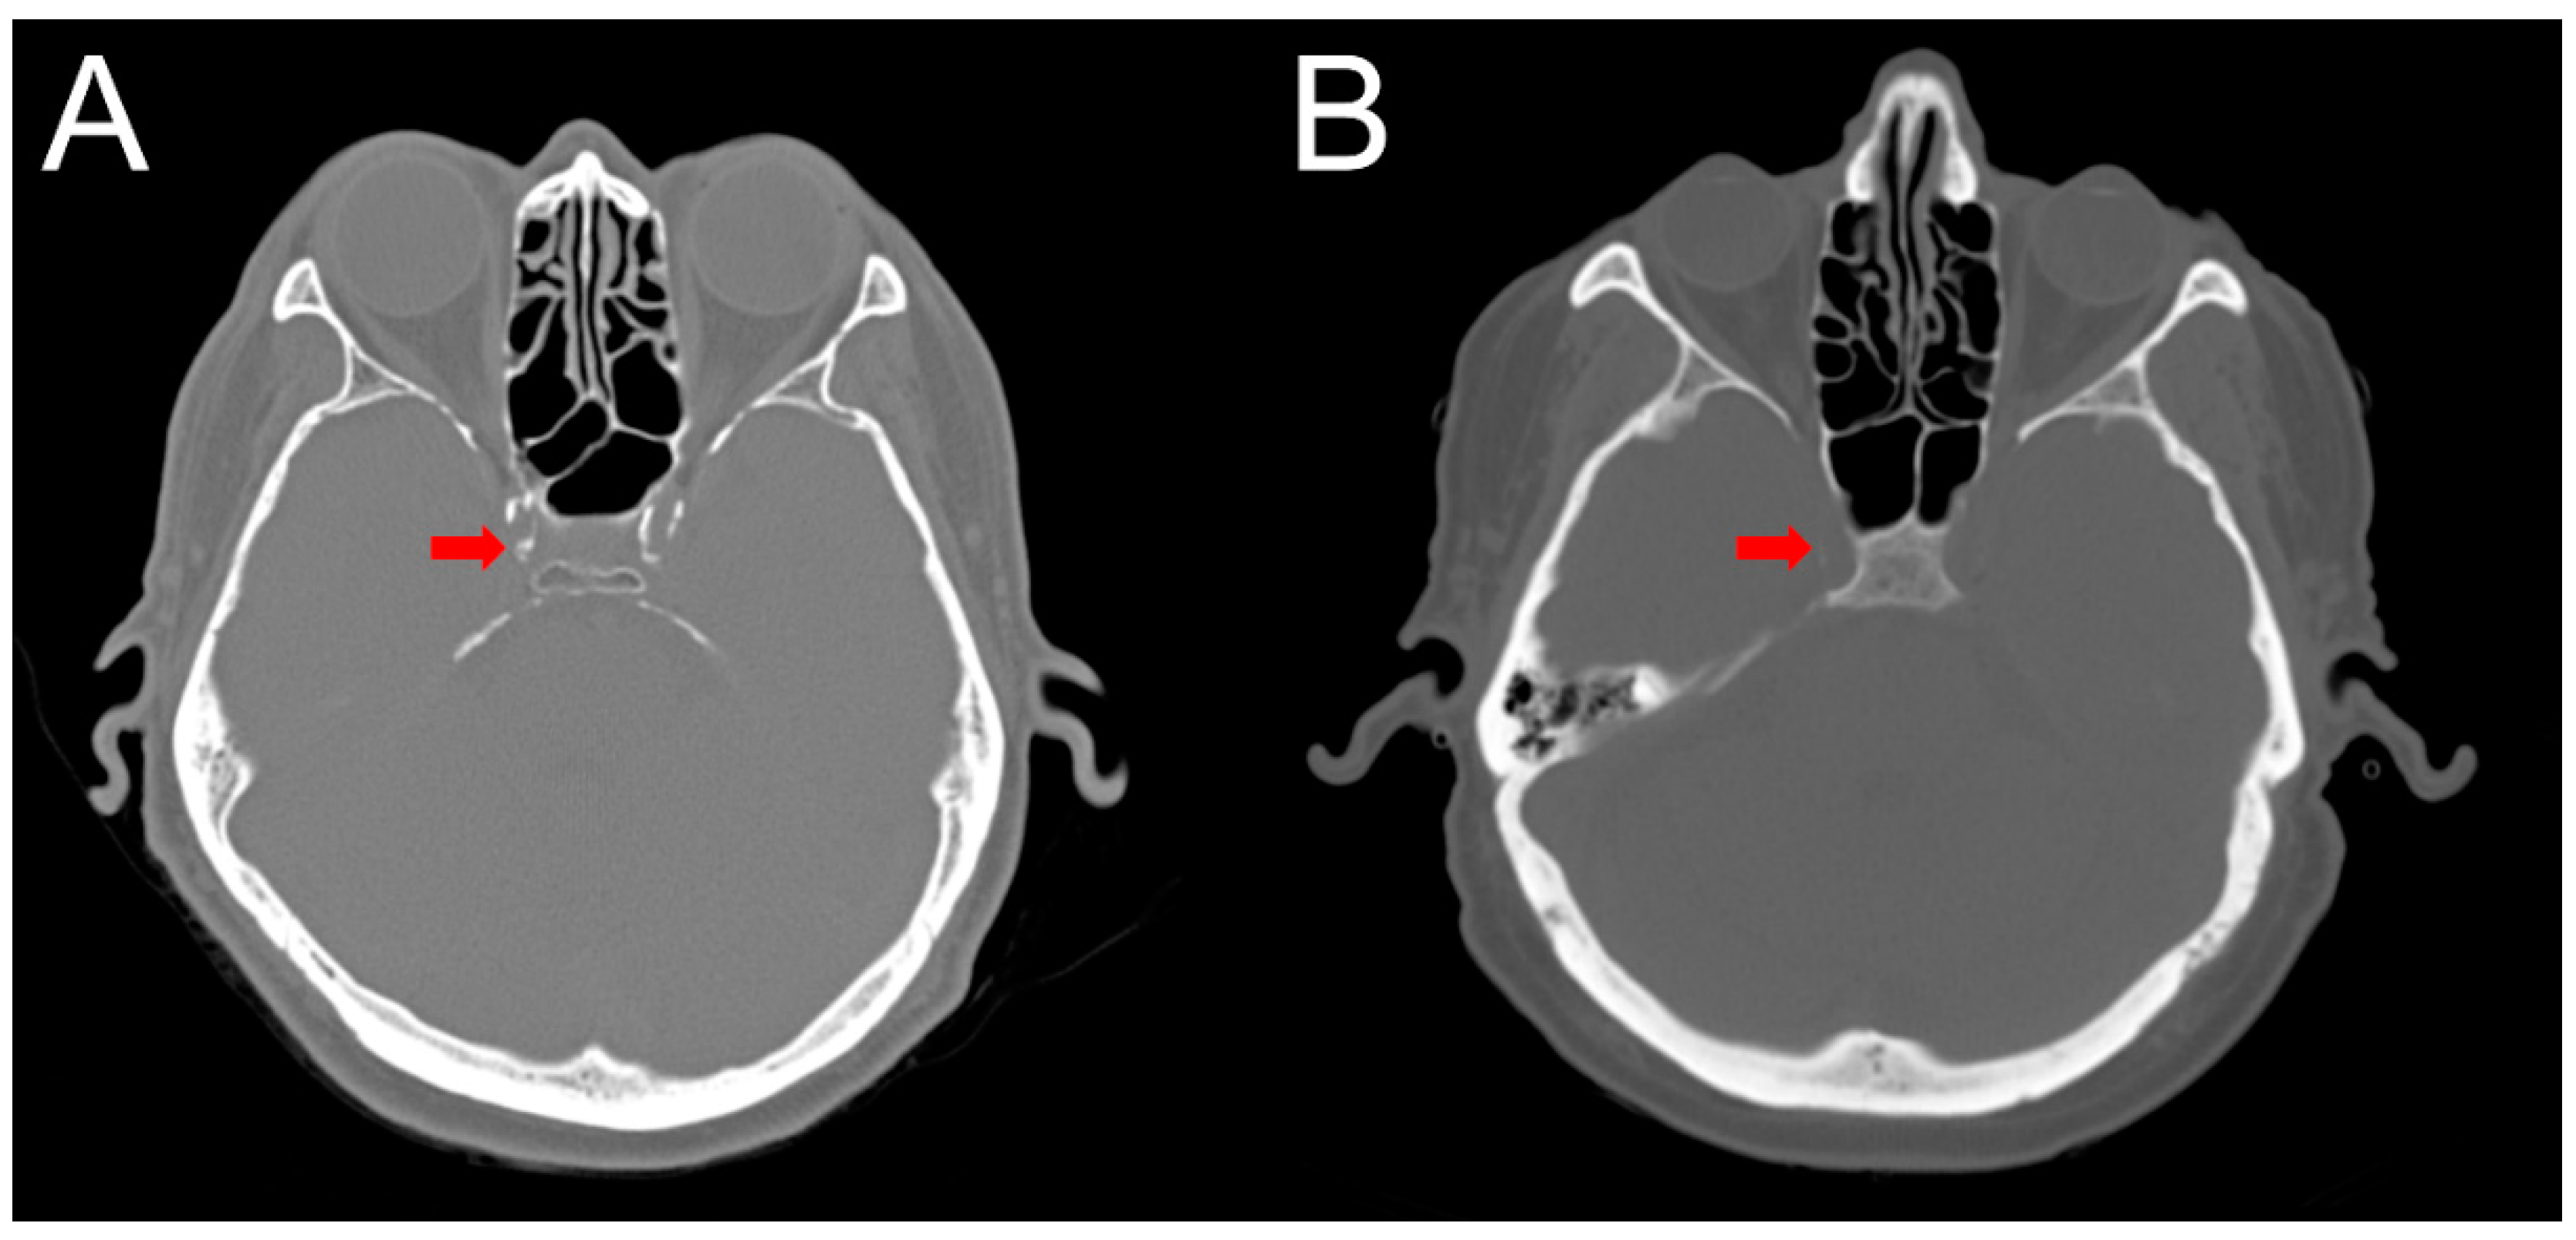

2.4. Intracranial Calcification

4.5. Clinical Outcomes